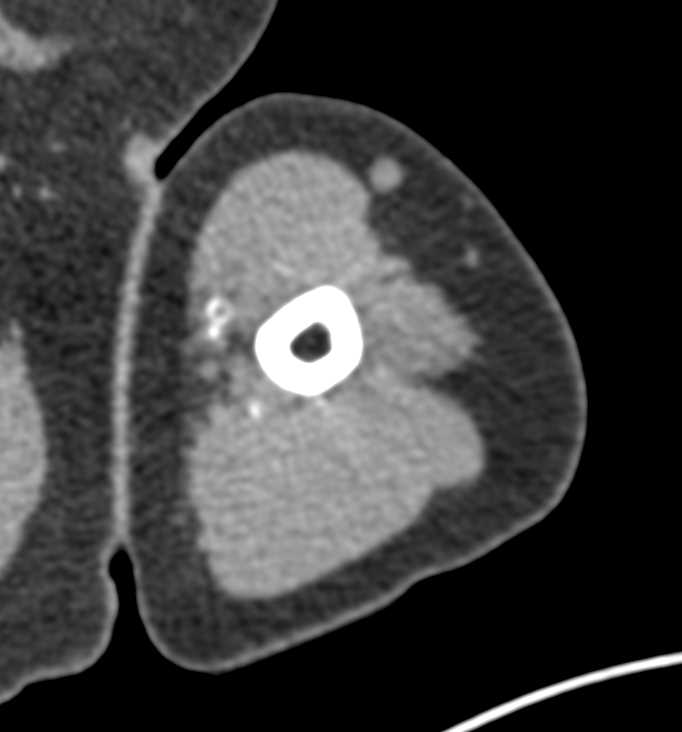

Brachial Artery Occlusion